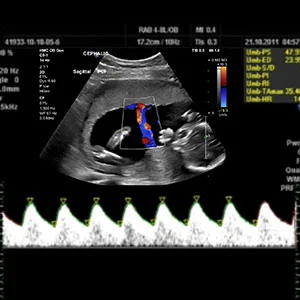

A Doppler ultrasound measures fetal blood flow and circulation in the uterus and umbilical cord. This Color Doppler imaging uses sound waves to visualize blood flow in the placenta, umbilical artery, or fetal heart. It helps assess the baby’s well-being (oxygen and nutrition supply). Lomash Health Care Center offers comprehensive Doppler scans for high-risk pregnancies (e.g. pre-eclampsia, diabetes) or as ordered by your obstetrician. Doppler is typically done in the second or third trimester or as needed to monitor fetal health.

- Purpose: Detects abnormal blood flow (e.g. in umbilical artery) that might signal fetal distress or growth issues. For example, Doppler can identify decreased blood flow in the umbilical artery of a growth-restricted baby.

- What does Doppler ultrasound show? It shows blood flow velocities in fetal and uterine vessels. Abnormal flow can indicate issues like placental insufficiency.